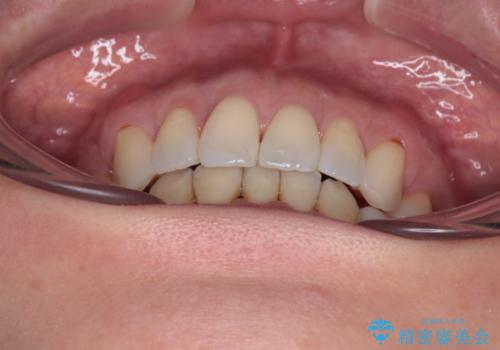

当初目論見通り、左右奥歯の咬み合わせはしっかりとさせることができました。

下唇に跡がつくほど飛び出していた上顎前歯も引っ込み、満足のいく仕上がりとなりました。